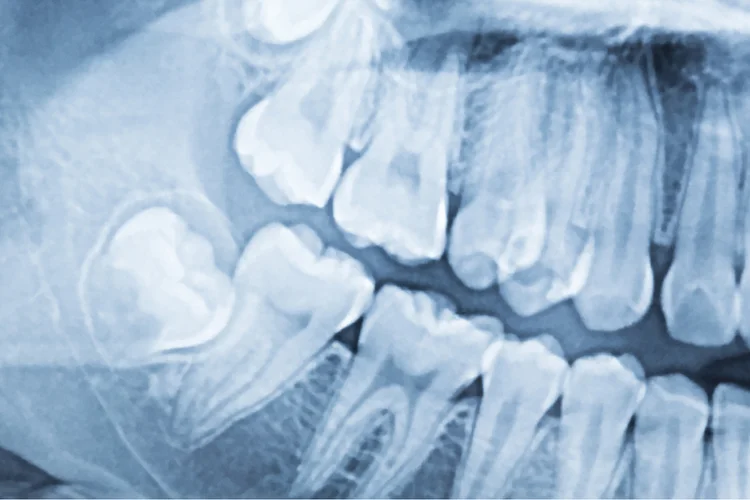

- Dental X-rays to evaluate root positioning, spacing and the condition of the jawbone.